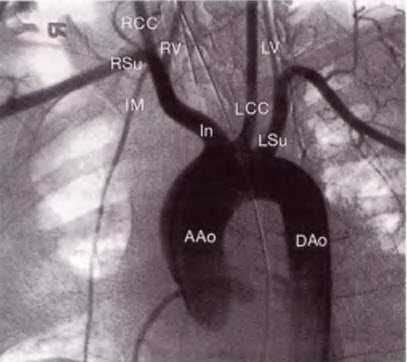

Рис. 14.2. Дуга аорты соединяет восходящий (ААо) и нисходящий отделы аорты (DАо). От дуги аорты отходят три крупных артериальных ствола: справа - брахиоцефальный ствол (In), левее - левая общая сонная артерия (LCC) и затем - левая подключичная артерия (LSu). Брахиоцефальный ствол делится на правую общую сонную артерию (ВСС) и правую подключичную артерию (RSu). Правая и левая позвоночные артерии (RV, LV) отходят от подключичной артерии, хотя на данной ангиограмме это не совсем четко видно. Внутренняя грудная артерия также отходит от подключичной артерии.